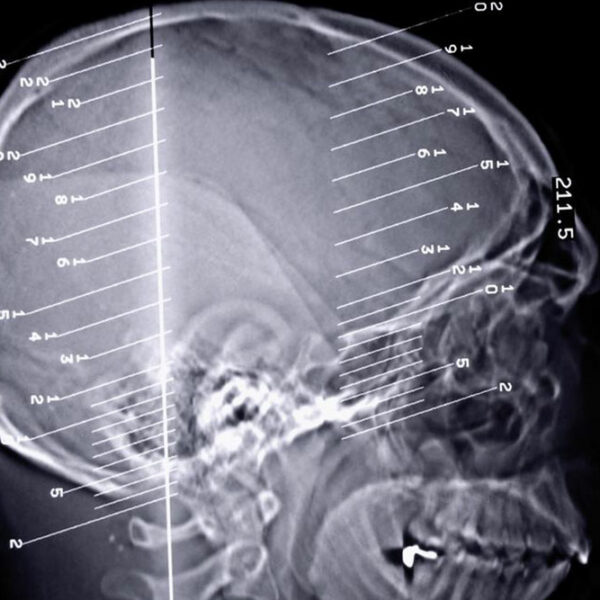

Epilepsy is a dreaded disorder, especially since it is connected to the dysfunctioning of the brain. The brain plays a pivotal role in the functioning of the human body and any kind of issue can lead to severe complications. The disorder is related to the dysfunctioning of the central nervous system in the brain. When the nerve cells in the brain send out wrong signals to the body, the result may be moderate to severe seizure.